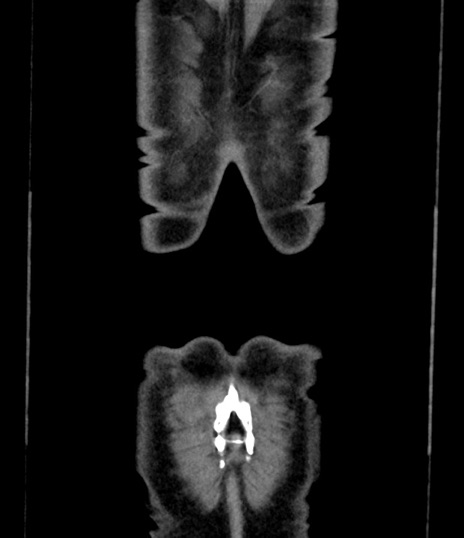

症例8(冠状断像)

症例

【症例】 60歳代男性

【主訴】 黒色吐物

【現病歴】 4日前から嘔気自覚、2日前の朝食後にも嘔気あり、自分で手で嘔吐反射起こし嘔吐したところ血が混ざっていたため受診。

【既往歴】 5年前汎発性腹膜炎を伴う急性虫垂炎で手術、高血圧、前立腺肥大症、高脂血症

【身体所見】 腹部正中に手術癩痕あり 腹部平坦・軟圧痛なし膨満感あり

【データ】WBC 8400、CRP 4.54